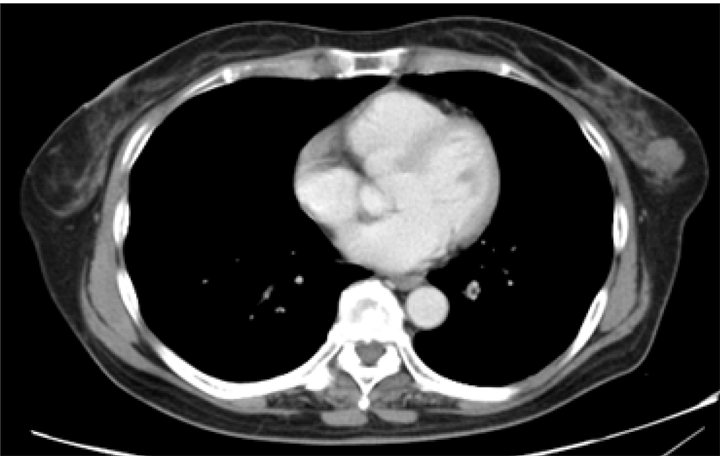

A 56-year-old Japanese asymptomatic female was admitted to our hospital with a diagnosis of sigmoid colon cancer. Computed tomography (CT) scan of her chest and abdomen was done as a preoperative examination of her colon cancer, and showed a nodule in the left breast. (Figure 1) The patient had no family history of breast cancer, no history of mammary trauma or biopsy and no history of lipid metabolism abnormality.

Figure 1: Computed tomography scan of chest showing a nodule in the left breast.